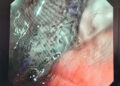

2.3. Quy trình can thiệp mạch vành bằng Stent với giá đỡ tự tiêu:

Giống như quy trình can thiệp mạch vành bằng Stent với giá đỡ Kim loại, tuy nhiên cần tuân thủ chặt chẽ 5 bước như sau:

– Tiến hành nong ĐMV bằng bóng thường nhiều lần với áp lực tăng dần để sao cho tỷ lệ đường kính bóng thường/ ĐMV = 1/1.

– Đo đường kính cũng như chiều dài đoạn ĐMV bị tổn thương sau khi tiêm Nitroglycerin trong lòng ĐMV(0,1-0,2mg).

– Đặt Stent tự tiêu phù hợp về đường kính cũng như chiều dài vào vị trí tổn thương.

– Nong Stent tự tiêu bằng bóng áp lực cao (NC) ít nhất16 bar (sao cho: ĐK Nominal Stent < ĐK bóng NC ≤ ĐK Nominal Stent + 0,5).